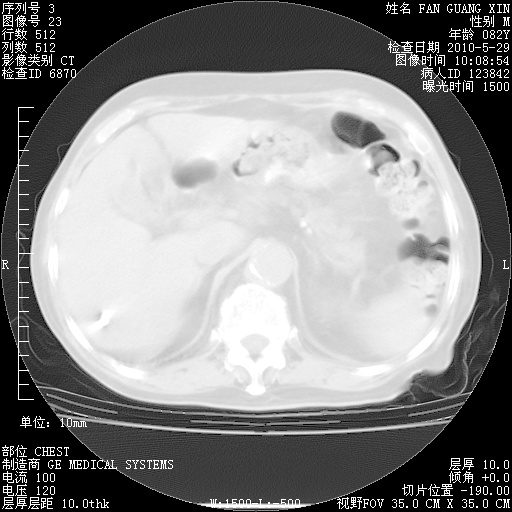

再治疗10天后的肺部CT

再治疗10天后的肺部CT 纵膈窗

肺部体征:呼吸25次/分,心率100次/分,呼吸音增粗。无干湿罗音。

血常规:15.36×10 [sup]9[/sup]/L  N0.92  L0.036  M0.045 ESR 27mm/h。

血生化:白蛋白33.30g/L  球蛋白23.67g/L  CRP 32.82mg/L 肝肾功能正常。电解质正常。

从白细胞总数和中性比例看好像合并感染。肺部纹理好像比上次多,支气管炎?其他感染?

阅读此次胸部CT,肺间质渗出性改变较入院时有吸收。目前从体温、白细胞、中性分叶明显增高,肯定存在细菌感染(发生医院感染哦,若无消化道及泌尿系统等感染的依据,肺部感染可能大)。若你院头孢哌酮舒巴坦钠耐药率较高,同意你的方案,若48小时体温仍高,可考虑使用碳青霉稀类抗菌药物,同时可予超声雾化、注意滴数时加大液体量。白蛋白33.30g/L较低哦,需加强营养等支持治疗。